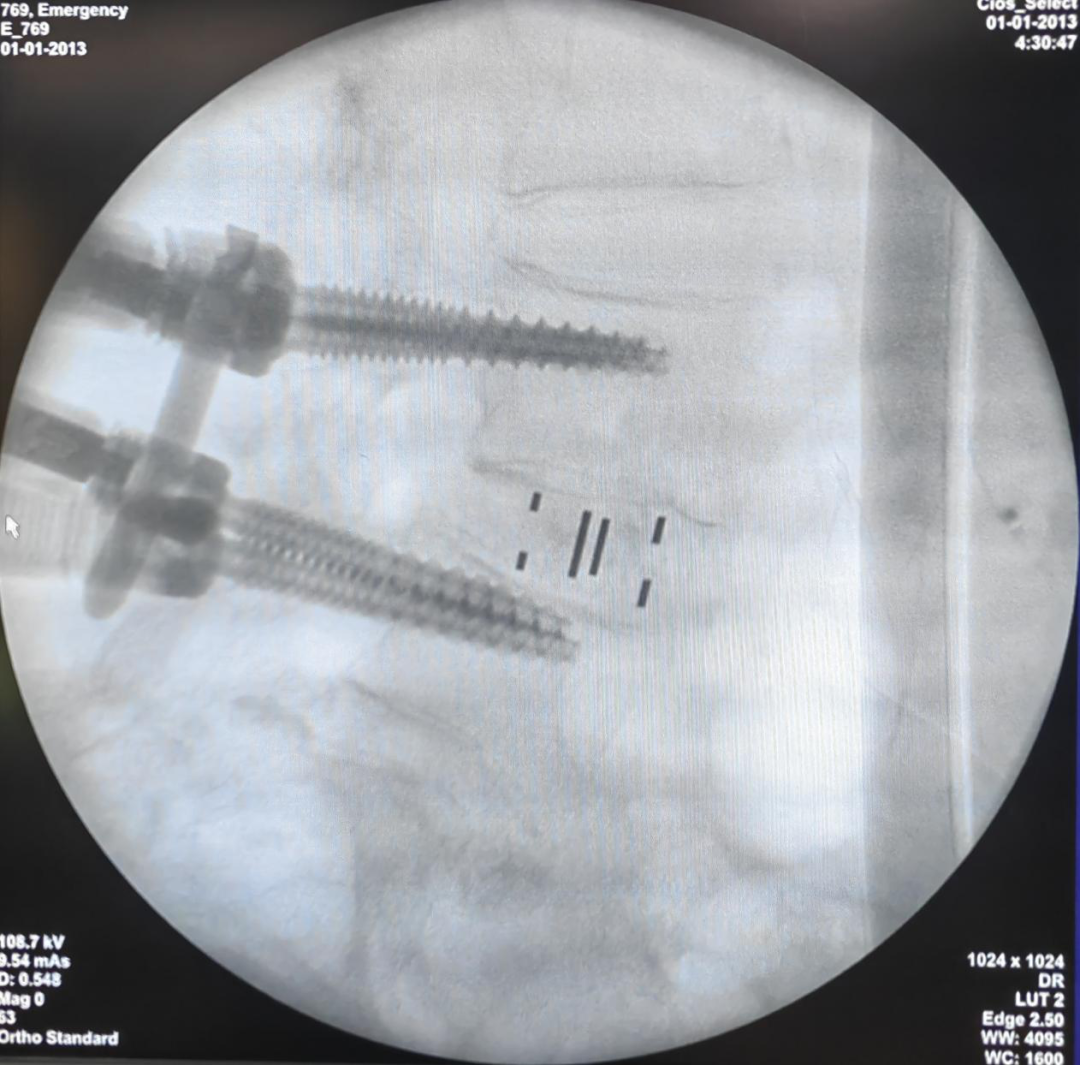

3月14日,张文捷团队协助该院完成首例OLIF手术,成功为一名69岁腰椎滑脱症患者解除痛苦,受到患者及其家属肯定。这是张文捷团队与防城港市中医医院脊柱骨病科首次的合作。

张文捷和防城港市中医医院覃正仕主任进行OLIF手术

OLIF完成手术照片